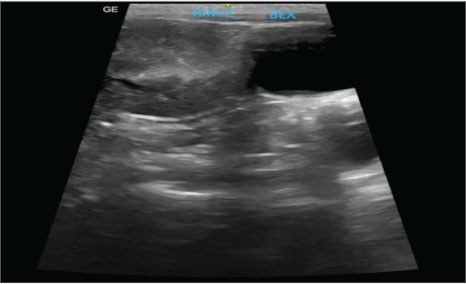

AbstractBackground: This report describes the first documented case of renal agenesis associated with ectopia of the contralateral kidney in a feline in veterinary medicine. Unilateral renal agenesis is a rare congenital anomaly characterized by the complete absence of one kidney. Renal ectopia, in turn, refers to the anomalous location of the kidney and is a rare condition. The simultaneous occurrence of these anomalies is extremely uncommon. Case Description: A 2-year-old spayed female mixed-breed cat presented with apathy, hyporexia, and vomiting. Laboratory tests revealed azotemia, and imaging tests confirmed the absence of the right kidney and the ectopic position of the left kidney, as well as alterations compatible with chronic kidney disease. Abdominal ultrasonography and excretory urography confirmed the diagnosis. Conclusion: Coexisting renal agenesis and ectopia are rare conditions in humans, and there are no reports of them in felines. Despite its rarity, the condition is compatible with life, as long as it is diagnosed early and continuously monitored. Keywords: Anomaly, Excretory urography, Rareness. IntroductionEmbryological development is a highly complex process that requires the precise and synchronized activation of molecular signals at specific moments to ensure adequate organ and system generation (Cohen et al., 2004). When these signs do not occur at the correct time, development can follow an atypical course, resulting in anomalies, such as agenesis, characterized by the complete absence of an organ (Cuckow et al., 2001). Unilateral renal agenesis is a rare congenital anomaly characterized by the complete absence of the kidney. It has been reported in different species, including dogs (Morita et al., 2005), cats (Dykeman, 2020), birds (Oliveira et al., 2020), mice, and humans (González Mediero et al., 1997; De Tomasi et al., 2017). It is even more rarely found when associated with other anomalies, such as ectopia of the contralateral kidney (Oliveira et al., 2020; Plutecki et al., 2023). Renal ectopia, defined by the anomalous location of one or both kidneys, is a rare condition that is usually an incidental finding in humans (Babu et al., 2015) and animals (Allworth and Hoffmann, 1999). The simultaneous occurrence of renal agenesis and ectopia is rarely described in the medical literature (Maachi et al., 2024), and to date, there are no documented reports in the veterinary literature. The diagnosis of renal ectopia and agenesis is obtained through imaging tests, such as radiography, ultrasound, and excretory urography; they allow the identification of the anomalous location of the kidney, associated structural alterations, and the absence of the organ in the case of agenesis (Allworth and Hoffmann, 1999; Rajabioun et al., 2017). This report describes the first documented case of renal agenesis associated with ectopia of the contralateral kidney in a feline, highlighting the diagnostic methods used, therapeutic approach, and subsequent clinical management. Case DetailsA 2-year-old spayed female mixed-breed adult cat weighing 2.15 kg presented with apathy, hyporexia, and acute-onset emesis episodes. The patient’s medical history included previous exams performed at 6 months of age, with negative results for FIV and FeLV (SNAP FIV/FeLV Combo-Idexx® Test), while living with four healthy felines in the same environment. On physical examination, moderate dehydration (7%) was identified, with systolic blood pressure (SBP) of 155 mmHg, measured using the Doppler method, and no other relevant clinical changes. Laboratory tests showed azotemia: creatinine serum: 2.2 mg/dl [reference interval: 0,6–1,6 mg/dl]; urea: 117 mg/dl [reference interval: 10–56 mg/dl], and no relevant changes in the blood count. Urinalysis and urine protein-to-creatinine ratio (UPC) were also performed, revealing a low urine specific gravity (USG: 1.015) (reference interval: USG >1,035) and a UPC of 0.7 (reference interval: UPC < 0,5). The patient was admitted for dehydration correction with intravenous fluid therapy using lactated Ringer’s and supportive therapy for vomiting and hyporexia, which included maropitant citrate (0.1 ml/kg, s.c., SID) and mirtazapine (3.75 mg/animal, PO, every 48 hours). Abdominal ultrasound examination revealed the left kidney in an ectopic position in the left caudal region of the abdomen, adjacent to the bladder. The organ had irregular contours, measuring approximately 3.42 cm in length along the longitudinal axis, with moderate loss of internal structure and reduced corticomedullary differentiation, consistent with chronic nephropathy (Fig. 1). The right kidney was not identified, and the other abdominal organs were within normal limits. Ultrasound findings were consistent with left renal ectopia.

Fig. 1. Ultrasound image showing the left kidney in an ectopic position in the left caudal region of the abdomen, close to the bladder. The organ presented with irregular contours, moderate loss of internal structure, and reduced CM differentiation. Once the patient was stabilized and after considering the absence of the right kidney and atypical location of the left, excretory urography was performed with intravenous administration of iodinated contrast (Omnipaque ®) at a dose of 600 mg/kg via access to the cephalic vein in a rapid bolus to better elucidate the condition. Before contrast media administration, plain abdominal radiographs were performed in ventrodorsal (VD), oblique (the X-ray entered the body through the right ventrolateral side and exited through ventrolateral on the left side), and right lateral projections. All projections showed the absence of the right renal silhouette, while the left kidney was located in the caudal portion of the abdominal cavity, presenting slightly lobulated contours and measuring 3.96 cm in length (Fig. 2A).